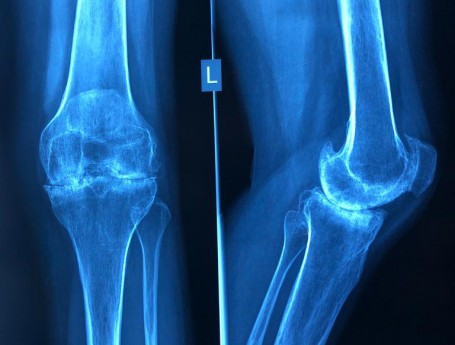

Knee Pain

Knee Exam

Knee